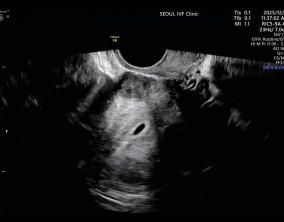

눈물로 실감한 아홉 번째 주

이경훈 원장님은 검사를 통해 나온 수치와 결과에 대해 자세히 설명해 주시고, 상황에 맞는 여러 방법을 함께 제시해 주셔서 큰 신뢰와 감사함을 느꼈습니다. 불안을 혼자 짊어지…